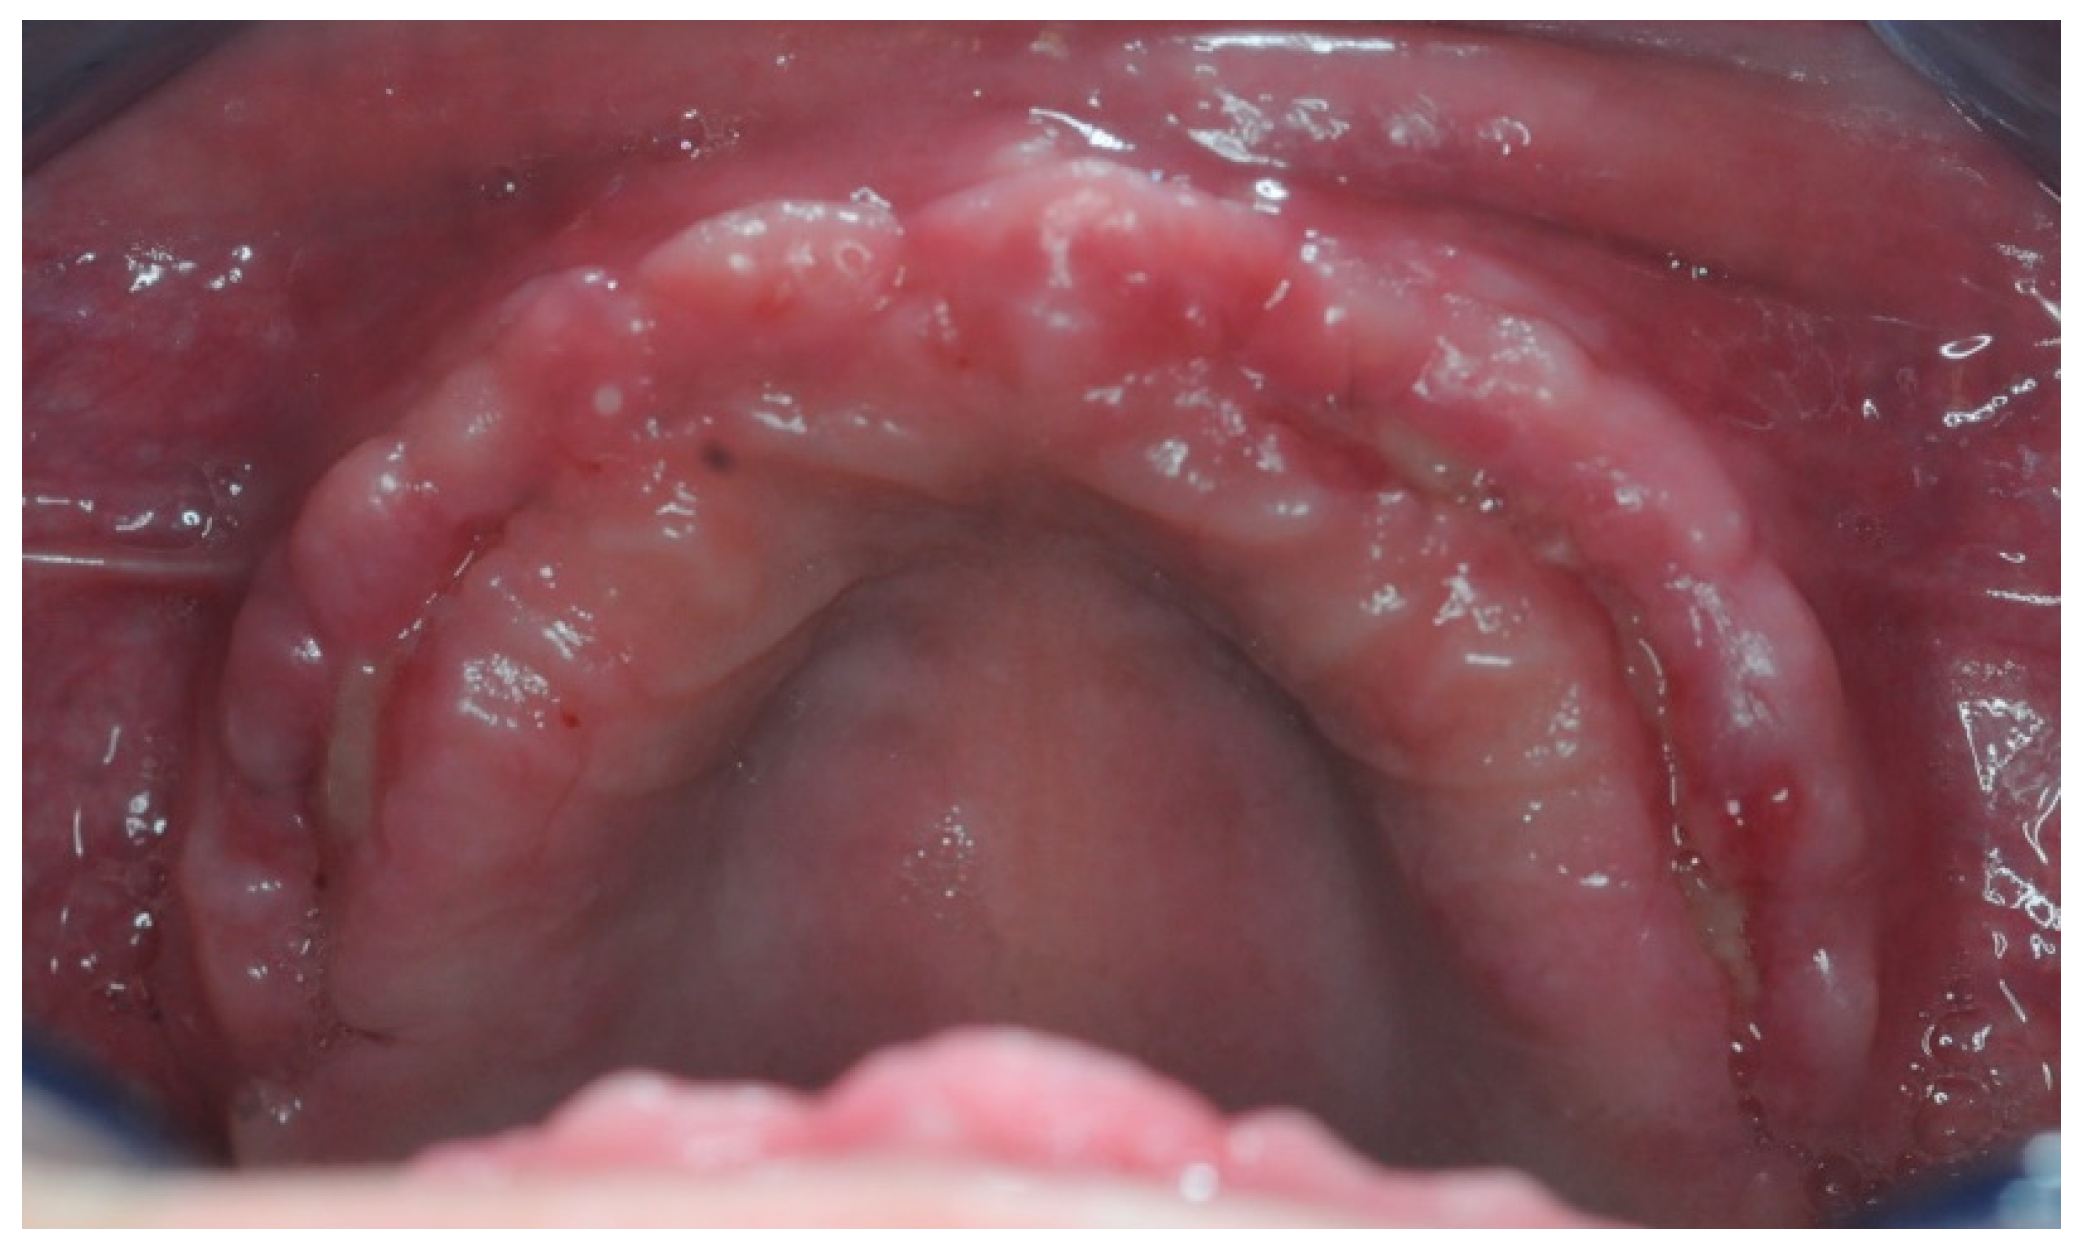

3.4. Soft Tissue Management